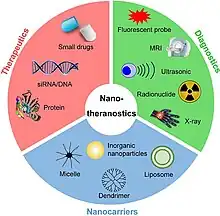

Theranostics, also known as theragnostics,[1] is a technique in personalised medicine and nuclear medicine where a one radioactive drug is used to identify (diagnose) and a second radioactive drug is used to treat cancerous tumors.[2][3][4]

In other words, theranostics combines radionuclide imaging and radiation therapy which targets specific biological pathways. Technologies used for theranostic imaging include radiotracers, contrast agents and positron emission tomography.[3][5] It has been used to treat thyroid cancer and neuroblastomas.[3]

Targeted drug delivery systems facilitate the selective delivery of therapeutic agents to specific disease sites while minimizing off-target effects. These systems employ strategies, such as nanoparticles, liposomes, and micelles, to encapsulate drugs and enhance their stability, solubility, and bioavailability.[14] By incorporating diagnostic components, such as imaging agents or targeting ligands, into these delivery systems, clinicians can monitor drug distribution and accumulation in real-time, ensuring effective treatment and reducing systemic toxicity. Targeted drug delivery systems hold promise in the treatment of cancer, cardiovascular diseases, and other conditions, as they allow for personalized and site-specific therapy.[14]

Nanomedicine refers to the use of nanoscale materials for medical applications. In theranostics, nanomedicine offers opportunities for targeted drug delivery, imaging, and therapy.[6] Nanoparticles can be engineered to carry therapeutic payloads, imaging agents, and targeting ligands, allowing for multimodal theranostic approaches. These nanocarriers can enhance drug stability, improve drug solubility, and enable controlled release at the disease site. Additionally, nanomaterials with inherent imaging properties, such as quantum dots or gold nanoparticles, can serve as contrast agents for imaging.[18]